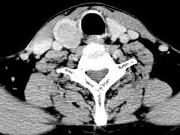

问题 男,43岁,右颈部扪及一包块,CT如图所示,应诊断为()

选项 A.甲状腺腺瘤 B.甲状腺腺癌 C.结节性甲状腺肿 D.甲状腺原发淋巴瘤 E.甲状腺转移瘤

答案 A